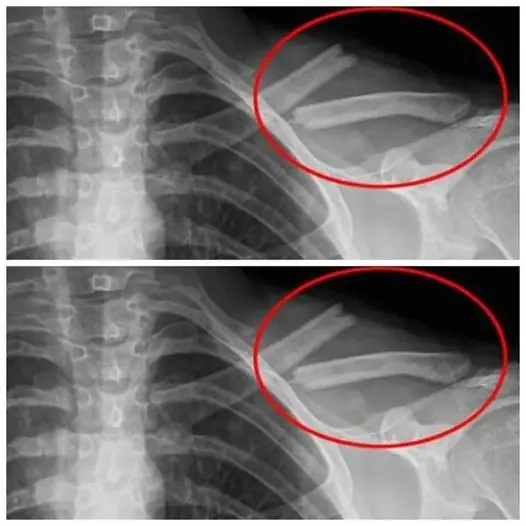

นพ.เหอ ตงจิ่น หัวหน้าแผนกโรคหัวใจของโรงพยาบาล ระบุว่า ผลการตรวจพบว่าผู้ป่วยมีภาวะ น้ำท่วมปอดเฉียบพลัน ส่งผลให้ระดับออกซิเจนในเลือดลดลงอย่างรวดเร็ว แพทย์จึงต้อง ใส่ท่อช่วยหายใจทันที และย้ายผู้ป่วยเข้าห้องผู้ป่วยวิกฤต

ด้าน นพ.หลิน เหวินเป่ย หัวหน้าแผนกผู้ป่วยวิกฤต เปิดเผยเพิ่มเติมว่า นอกจากภาวะน้ำท่วมปอดเฉียบพลันแล้ว ผู้ป่วยยังมี ภาวะหัวใจล้มเหลวและหลอดเลือดหัวใจตีบอุดตัน แพทย์ประเมินว่าอาการอยู่ในขั้น วิกฤต มีความเสี่ยงเสียชีวิตสูง หากไม่ได้รับการรักษาอย่างทันท่วงที

ผู้ป่วยได้รับการ ใส่ขดลวด (stent) เพื่อเปิดหลอดเลือดหัวใจ พร้อมใช้ยารักษาประคับประคอง โชคดีที่หลังเข้ารับการรักษาหลายวัน อาการของนายหลี่ค่อย ๆ ดีขึ้น พ้นขีดอันตราย และถูกย้ายไปยังหอผู้ป่วยทั่วไป พร้อมเข้ารับการฟื้นฟูร่างกายภายใต้การดูแลของทีมแพทย์และพยาบาล